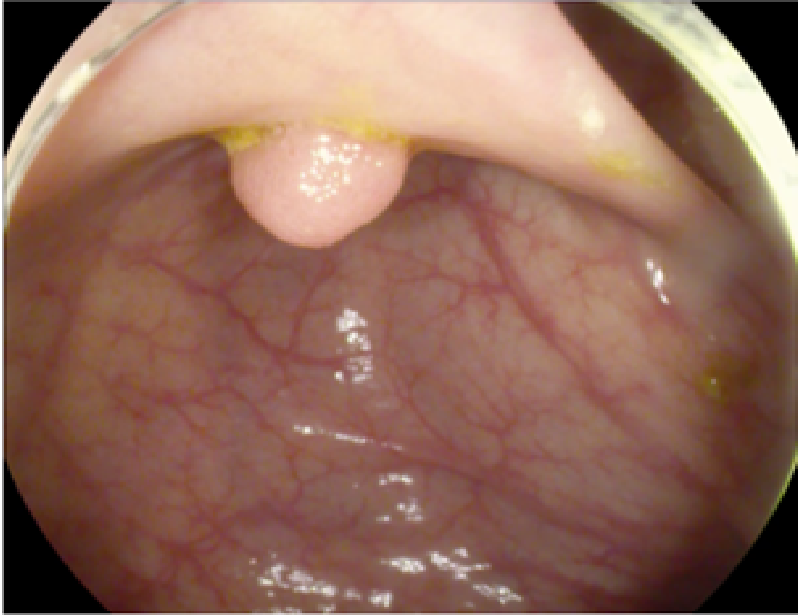

4.1 Dataset Specifications and Augmentation

The study used a publicly available dataset of polyp-frames obtained from the ETIS-Larib database [34], containing 196 polyp images. These images were obtained from 34 different colonoscopy videos of 44 different polyps with various appearances and sizes, having a resolution of 1225×96612259661225\times 966 pixels. The ground truth of polyp areas for polyp datasets is determined by expert video endoscopists. A CNN model trained with such a small amount of data is likely to be meaningless and unstable, so data augmentation was performed on the polyp dataset. Data augmentation had to be performed on the colonoscopy images by considering vivid variations. Otherwise over-fitting would have occurred. In a colonoscopy imagery, polyps exhibits large variations in location, color, and scale. Moreover, variations in brightness and definition also occur due varrying the view-point of the camera. Therefore, in addition to photometric distortions and geometric distortions, we also have considered zooming, shearing, and altering brightness as strategies for data augmentation.

For photometric distortions, we controlled brightness and contrast as an enhancement, while blurring by adding noise with a standard deviation (σ)𝜎(\sigma) of 1.0. Similarly, for geometric distortions, clock-wise rotation of the polyp images with angles of 90°90°, 180°180°, and 270°270° were performed. Zoom-in and zoom-out with zooming parameters such as 30.00% and 10.00% were performed to obtain different scales of polyp images. Lastly, shearing for both the x-axis and the y-axis was performed to shear the images from left to right and top to bottom, respectively. Fig. 4 shows photometric and geometric forms of image augmentation. In this way, we augmented the data set of the ETIS-Larib database from 196 polyp images to 2,156 images, which is more suitable for training the proposed deep CNN model.